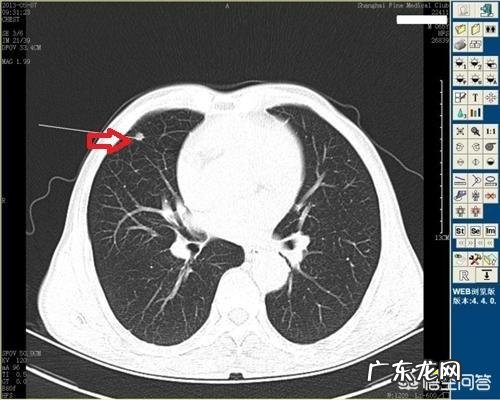

对于肺结核患者 , 如果胸部CT提示肺内出现了钙化 , 那么恭喜你 , 说明结核在好转、愈合 , 这是非常好的一个征兆 , 大家不用过度担心;相反 , 如果CT检查提示肺内为多发的斑片、结节等影像 , 而没有钙化 , 那么提示可能结核处于活动期 , 这个时候一定要积极进行正规的治疗 , 避免病情进一步进展 。

钙化是结核疾病演变过程中常见的结局之一 , 这是结核愈合的结果 , 是好事 , 说明结核已经好转了 。另外 , 肺部出现纤维化也是结核好转的征象 。很多人检查的时候发现肺部出现钙化灶或者纤维化很有可能以前感染过肺结核 , 经过治疗或者自身抵抗力战胜了结核杆菌 , 肺结核愈合之后遗留下来的痕迹 , 这是不用治疗的 。

结核活不活动也可以通过胸片或者肺部CT表现来判断 , 如果胸片或者肺部CT表现为边缘模糊不清的斑片影、空洞或者播散病灶 , 那就说明结核正在活动 , 正在损害我们的肺脏 , 这种肺结核就需要治疗 。